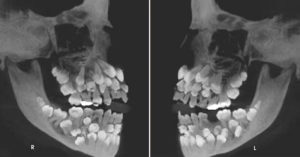

「我很高兴你尊重和照顾这根脚趾头。」原来这根属于Haley的脚趾头是因为短趾症(Brachymetatarsia),在十几年前的手术中被切除了。